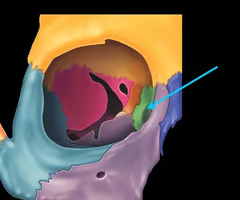

Optic canals (optic nerve)

Optic canals (optic nerve)

Lesser wing of the sphenoid bone

Greater wing of the sphenoid bone (“sphen”=wedge)

Greater wing of the sphenoid bone (“sphen”=wedge)

Cribriform plate of the ethmoid bone (notice olfactory formina in it - for olfactory nerves. Crista galli “rooster’s comb” dura mater attaches here)